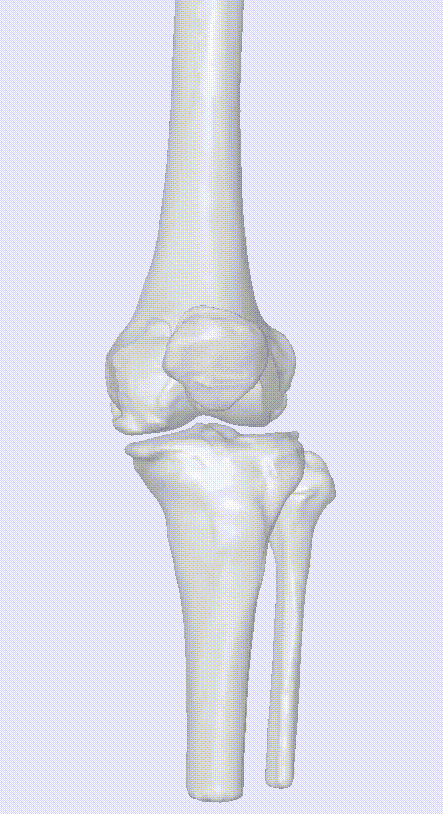

三维重建

图片

三维数据精准测量

灵犀AI基于患者二维影像学数据自动进行方案设计,避免了工程师设计可能出现的人为失误。通过三维重建、精准测量、自动规划截骨数据:自动假体选型、优化对位关系、确认截骨线位置等,生成可视化的《术前规划报告》。